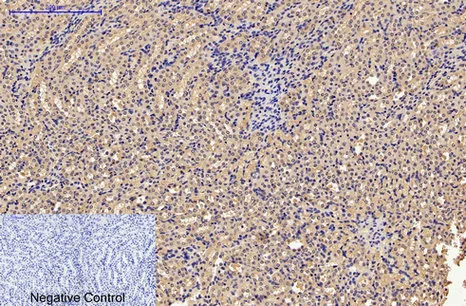

NSE(13E2)Mouse Monoclonal Antibody

Cat: AMM14910

Size1:50μL Price1:$118

Size2:100μL Price2:$220

Size3:200μL Price3:$380

Application:WB,IHC-P,IF-P,IF-F,ICC/IF

Reactivity:Human,Mouse,Rat

Conjugate:Unconjugated

Optional conjugates: Biotin, FITC (free of charge). See other 26 conjugates.

Gene Name:ENO2